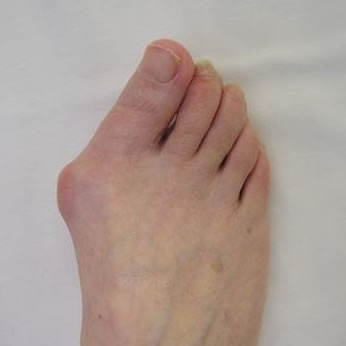

Bunion surgery aims to narrow the often widened forefoot and, thus eliminate or reduce the inner bump. As a result the big toe is straightened and no longer pushes across the lesser toes. The weight-bearing forces are, thus, redistributed, the big toe becomes more functional again and any pain in the ball of the foot (metatarsalgia) may also subside.

Several surgical techniques are available and Mr Weitzel will advise the patient of the most appropriate for her/his individual problem. This will often include a form of osteotomy (cutting and realigning of bone Fig 4) which is then fixed with internal implants such as screws and/or staples.